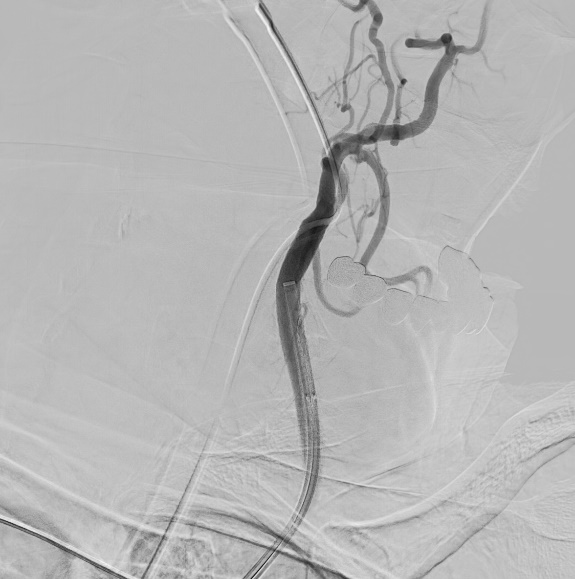

A microscopic photo illustrating carotid artery blockage

1- Carotid artery blockage in neck

a microscopic photo illustrating left middle cerebral artery clot

2- Left middle cerebral artery clot

a microscopic photo illustrating stent in carotid artery and clot removed from middle cerebral artery

3- Stent in carotid artery and clot removed from middle cerebral artery

Mechanical thrombectomy is the usual treatment when an ischemic stroke only involves one large brain-vessel blockage. It involves threading a catheter through the groin or wrist to reach the occluded vessel and remove the blood clot.

Treatment is more complex when a patient suffers a stroke with tandem occlusion. Doctors must decide between two endovascular options, treat the neck first or treat the brain first. Studies have shown benefits to both approaches:

• Neck first: For the antegrade approach, a balloon and stent are used to open the blocked carotid artery. Next, the blockage in the brain vessel is removed by threading a catheter through that freshly opened neck artery to the blood clot in the brain.

• Brain first: For the retrograde approach, the goal is to get the brain reoxygenated as quickly as possible to prevent further damage. A balloon is used to open the neck blockage just enough to get a catheter through to the brain blood clot. Once the brain vessel blockage is cleared, the doctor can back track to the ballooned neck artery and open it more firmly with additional ballooning and/or a stent.